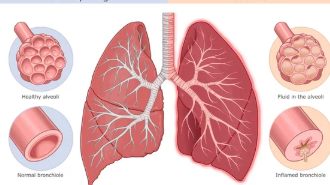

방사선 폐렴이 치료 없이 방치되면 폐 기능이 점점 악화될 가능성이 높습니다.

- 폐활량 감소:

폐가 딱딱해지는 섬유화 현상이 진행되면서 숨을 깊이 들이쉬기가 어려워지고, 폐활량이 감소합니다. - 산소 부족 증상:

피부가 푸르스름해지는 청색증이 나타나거나, 운동 중 어지러움이나 혼란 상태가 발생할 수 있습니다. - 만성 폐질환으로 진행 가능성:

초기 단계에서 치료하지 않으면 만성 폐섬유증으로 발전해 장기적인 호흡 문제가 생길 수 있습니다.